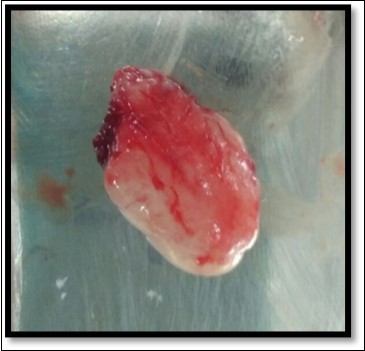

A 13year-old male patient reported to the Department of Pediatric and Preventive Dentistry with a chief complaint of the presence of a ‘lump’ in the lower right back region. The history revealed that the patient had buccal abscess in relation to 85 two months back for three days which reduced on medications. The tooth (85) exfoliated within 1 month and soon after the exfoliation, patient noticed a lump in that region. The lump was painless and increased in size in the last one month. Patient experienced discomfort in speech since the last one week. No abnormality or asymmetry was noted on extra-oral examination. Intraoral clinical examination revealed a painless, fibrous nodular mass with a sessile base in the right lower gingival margin extending from the mesial surface of 44 to distal surface of 45 on the lingual surface, measuring approximately 2 cm in diameter and showing a rough surface and color similar to that of the adjacent mucosa(Figure 1)

Figure 1.Pre operative size and extent of lesion

During the next visit local anesthesia was given. The lesion was excised with the help of soft tissue laser and sent for histological examination. (Figure 2) Histological report confirmed the lesion is Peripheral cemento-ossifying Fibroma. Histological analysis showed lesional tissue comprising of both trabecular bone and woven bone. Periphery of the lesion showed numerous globular and irregular cementum like calcification. In most areas these calcification coalesced with each other forming bigger calcification. The supporting connective tissue stroma was loose fibrillar with less cellularity. Detached overlying parakeratinized epithelium was observed in one area. (Figure 3) Post operative evaluation revealed normal healing after one month. (Figure 4)